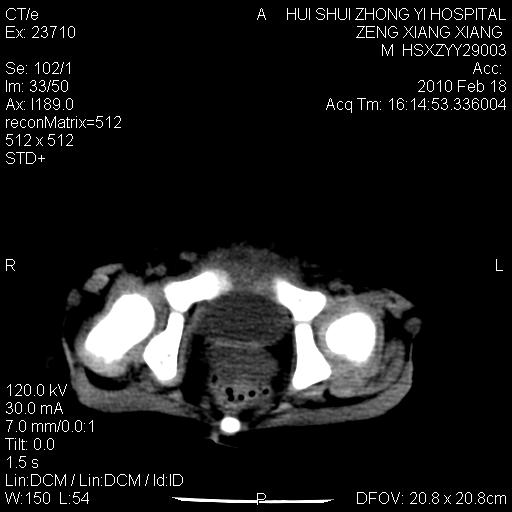

标题: PED3106:男,2岁,腹胀1月。 [打印本页]

标题: PED3106:男,2岁,腹胀1月。

定位腹膜后,肾上腺来源;

定性:恶性神经源性,肾上腺神经节母细胞瘤可能性大。

鉴别:肝母、肾母、肝脏中胚层错构瘤。

依据:年龄、有钙化,肾脏及肝脏受压移位。

肝母细胞瘤可能性大,右肾形态大体可见,不支持肾母细胞瘤,右肾移位不明显,肾上腺神经母细胞瘤可能性不大。